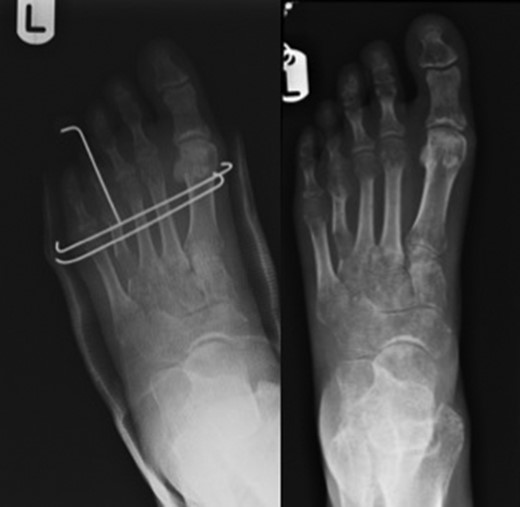

The majority of publications regarding gradual bone lengthening describe the use of unilateral external fixators with scant publications on the use of semi-circular external fixators [9] and none reporting the use of circular external fixators (Fig. 2).

Figure on the left showing trans-metatarsal K-wires in-situ along with the toe carrying wire cut and left alone. Figure on the right showing callus formation over distraction zone.